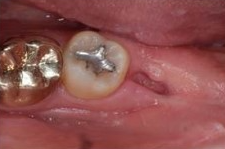

아래 케이스를 보면 위아래 사랑니가

정상 맹출되었으나 충치가 진행되어

주변치까지 영향을 주기 전에

발치를 진행하였습니다.

사랑니 발치 후 회복과정 한 눈에 보기 / 강남역 사랑니 강남레옹치과